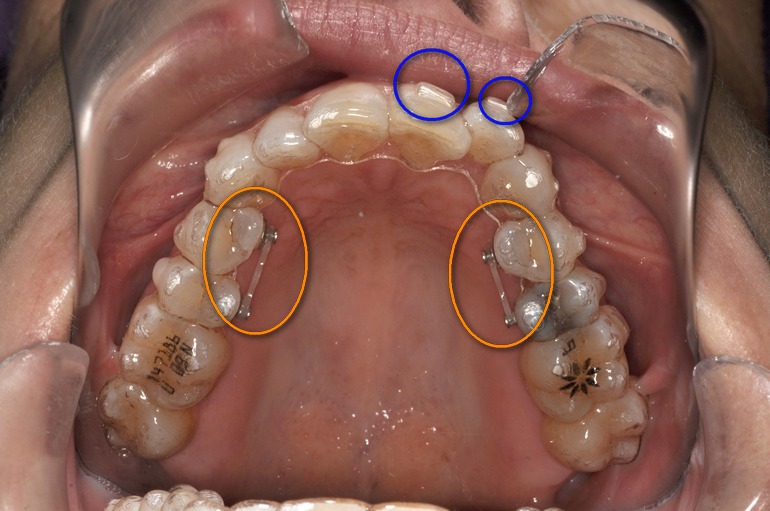

Con el cuarto alineador han venido los ataches. Unas pequeñas cuñas pegadas en los dientes que ayudarán al alineador a que mueva los dientes en la dirección que quiere (he marcado algunos con círculos azules). Y con los ataches llega la incomodidad de extremar la limpieza cada vez que comes para que ningún resto de comida se quede enganchado a ellos. También me han colocado 4 botones en la parte interna de mis dientes superiores enganchados con una cadena para conseguir mayor presión (círculos naranjas). Esto no es necesario en todos los casos, pero sí en el mio. Mi lengua está continuamente tropezando con ellos. Una guerra que apaciguo con un poco de cera para que no se me hagan llagas. He llegado a la conclusión de que por muy invisible que sea no deja de ser una ortodoncia y requiere del esfuerzo y la paciencia del paciente. No obstante he visto el final del tratamiento y sigo muy motivada.